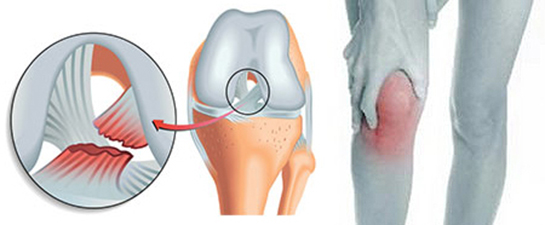

Diz kapağında çatlak belirtileri genellikle harekette yoğun ağrı, şişlik ve kısıtlı hareket kabiliyeti gibi durumlarla kendini gösterir. Bu tür belirtiler, diz kapağında bir sorun olduğuna işaret edebilir. Özellikle hareket sırasında hissettiğiniz ağrı, diz ekleminizde bir yaralanma veya hasar olduğunu gösterebilir.

Diz kapağında parmak çatlaması belirtileri yaşamış biri olarak, hareket ederken yoğun bir ağrı hissetmek ve dizin çevresinde şişlik oluşması oldukça rahatsız edici. Ayrıca, dizdeki sesli çatlama, bu durumu daha da kötüleştiriyor. Bu belirtilerle karşılaşan var mı? Nasıl bir çözüm buldunuz?

Sayın Ergüleç,

Diz kapağındaki parmak çatlaması ve bu duruma bağlı olarak yaşadığınız ağrı ve şişlik, oldukça rahatsız edici bir durum. Bu tür belirtiler, çoğu zaman tendonların, bağların veya kıkırdağın stres altında olduğunu gösterebilir. Özellikle hareket sırasında sesli çatlama, eklem sağlığı açısından dikkat edilmesi gereken bir durumdur.